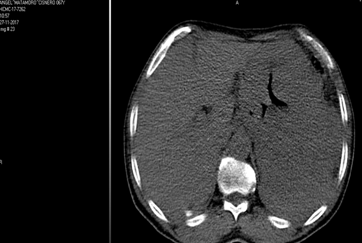

Tomografía Axial Computarizada (TAC) de abdomen: LOE gástrica que infiltra, bazo, lóbulo izquierdo del hígado, presencia de adenopatías del tronco celiaco y borde superior del páncreas. Con densidad variable, contornos bien definidos, sin variación luego de la administración de contraste. (Fig. 1)